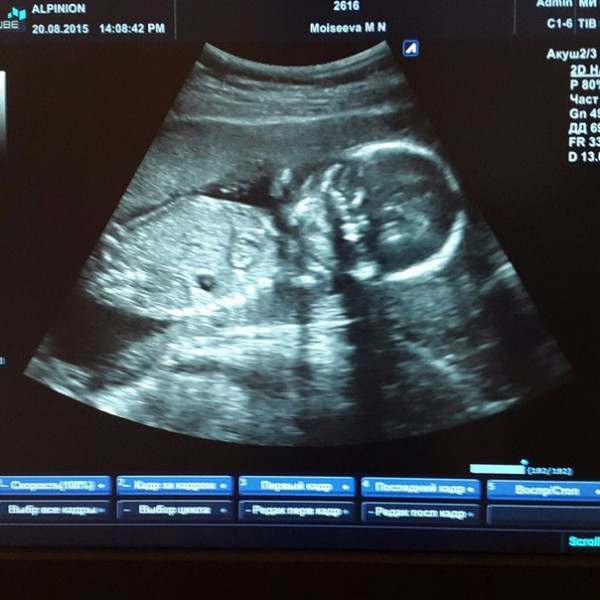

Фото Ребенка 20 Недель

Фото Ребенка 20 Недель 118 фотографий